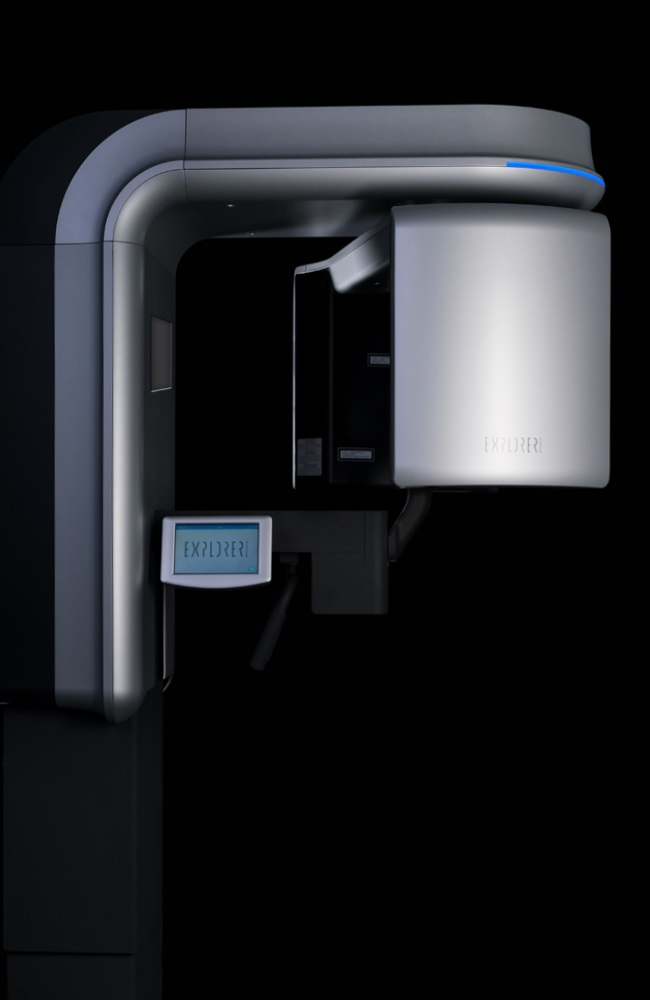

Com um dos maiores FOV do mercado, 150 mm x 160 mm, o PreXion3D EXPLORER pode exibir todas as estruturas anatômicas importantes do crânio em detalhes. O poderoso software de imagem ajuda a destacar e medir as áreas de interesse. Especialmente para cirurgia oral e maxilofacial, bem como na medicina do ouvido, nariz e garganta. A análise de imagens espaciais em grandes áreas ajuda a desenvolver as melhores opções de terapia.

que PreXion3D EXPLORER?

Os poderosos componentes do sistema do PreXion3D EXPLORER e a combinação extraordinária das mais precisas imagens 3D, com grandes detalhes e menor exposição à radiação, permitem diagnósticos confiáveis e planejamento digital para todas as indicações da odontologia moderna, como periodontologia, endodontia, implantodontia e cirurgia maxilofacial . O sistema de gerenciamento de pacientes foi projetado para comunicação segura dos dados do paciente em toda a rede do cliente podendo ser integrado à infraestrutura existente. Com a precisão e competência profissional da PreXion, os clientes têm o parceiro certo ao seu lado.